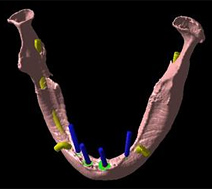

次に下側、下顎で水平でなく垂直に骨が溶けた場合どうなるのか?

上の顎と違い、下顎には大きい神経、血管が通っています。

下顎にはそういった大きい神経血管があるのです。

そのようなところに骨が溶け、バイ菌が血管の中に入ったら、何が起こるんでしょうか。